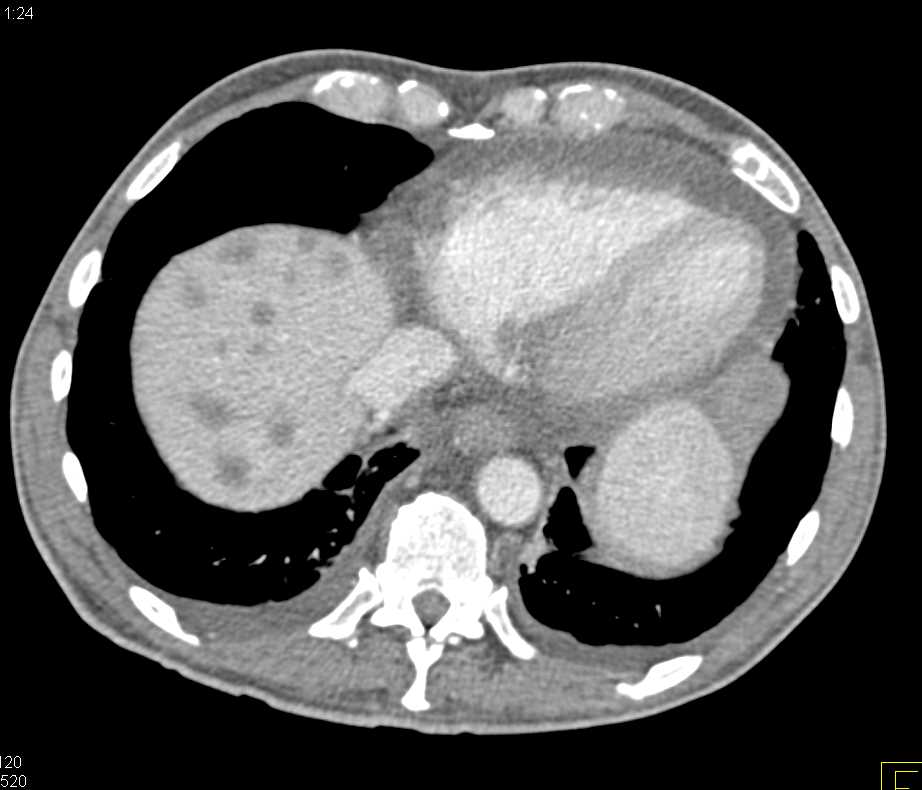

КТ диагностика тубоовариального абсцесса: Подходы и изображения